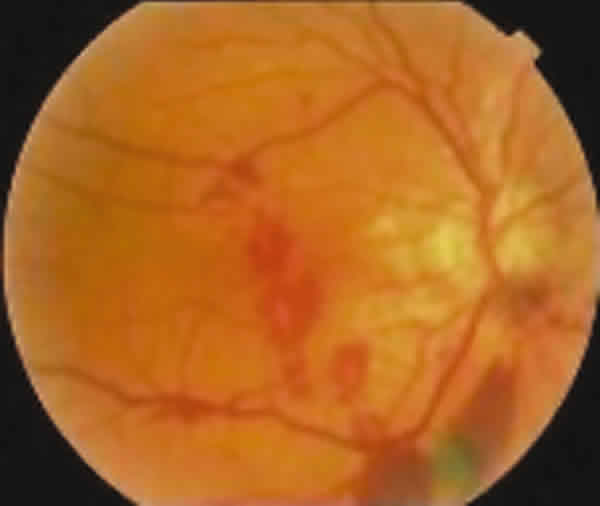

Fig. 2. Fondo de ojo izquierdo. Cicatriz disciforme. Estrías angioides peripapilares.